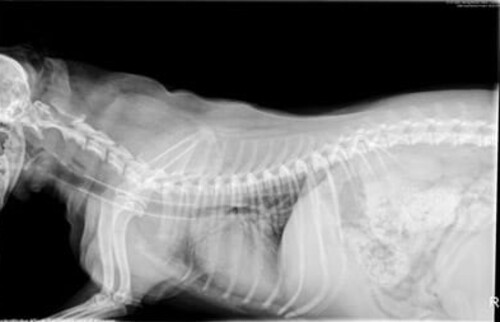

Röntgenbild einer Luftröhre mit einem Trachealstent.

Bei massiven Atemproblemen die auf die konservative Behandlung nicht ansprechen, kann die Luftröhre stabilisiert werden. Ein minimalinvasives Verfahren ist der Trachealstent. Dabei wird ein Gittergeflecht in die Luftröhre eingeführt, über dem instabilen Teil plaziert und aufgespannt. Dadurch wird der Luftweg wieder geöffnet und dauerhaft offen gehalten. Das Gittergeflecht wird von Schleimhaut überzogen und verbleibt lebenslang in der Luftröhre. Nicht jedem betroffenen Patienten hilft ein Trachealstent gleichermaßen. Ob Ihr Hund davon profitieren würde kann über klinische Untersuchungen in der Sprechstunde und mit Hilfe eine Spiegelung (Endoskopie) der Atemwege festgestellt werden.